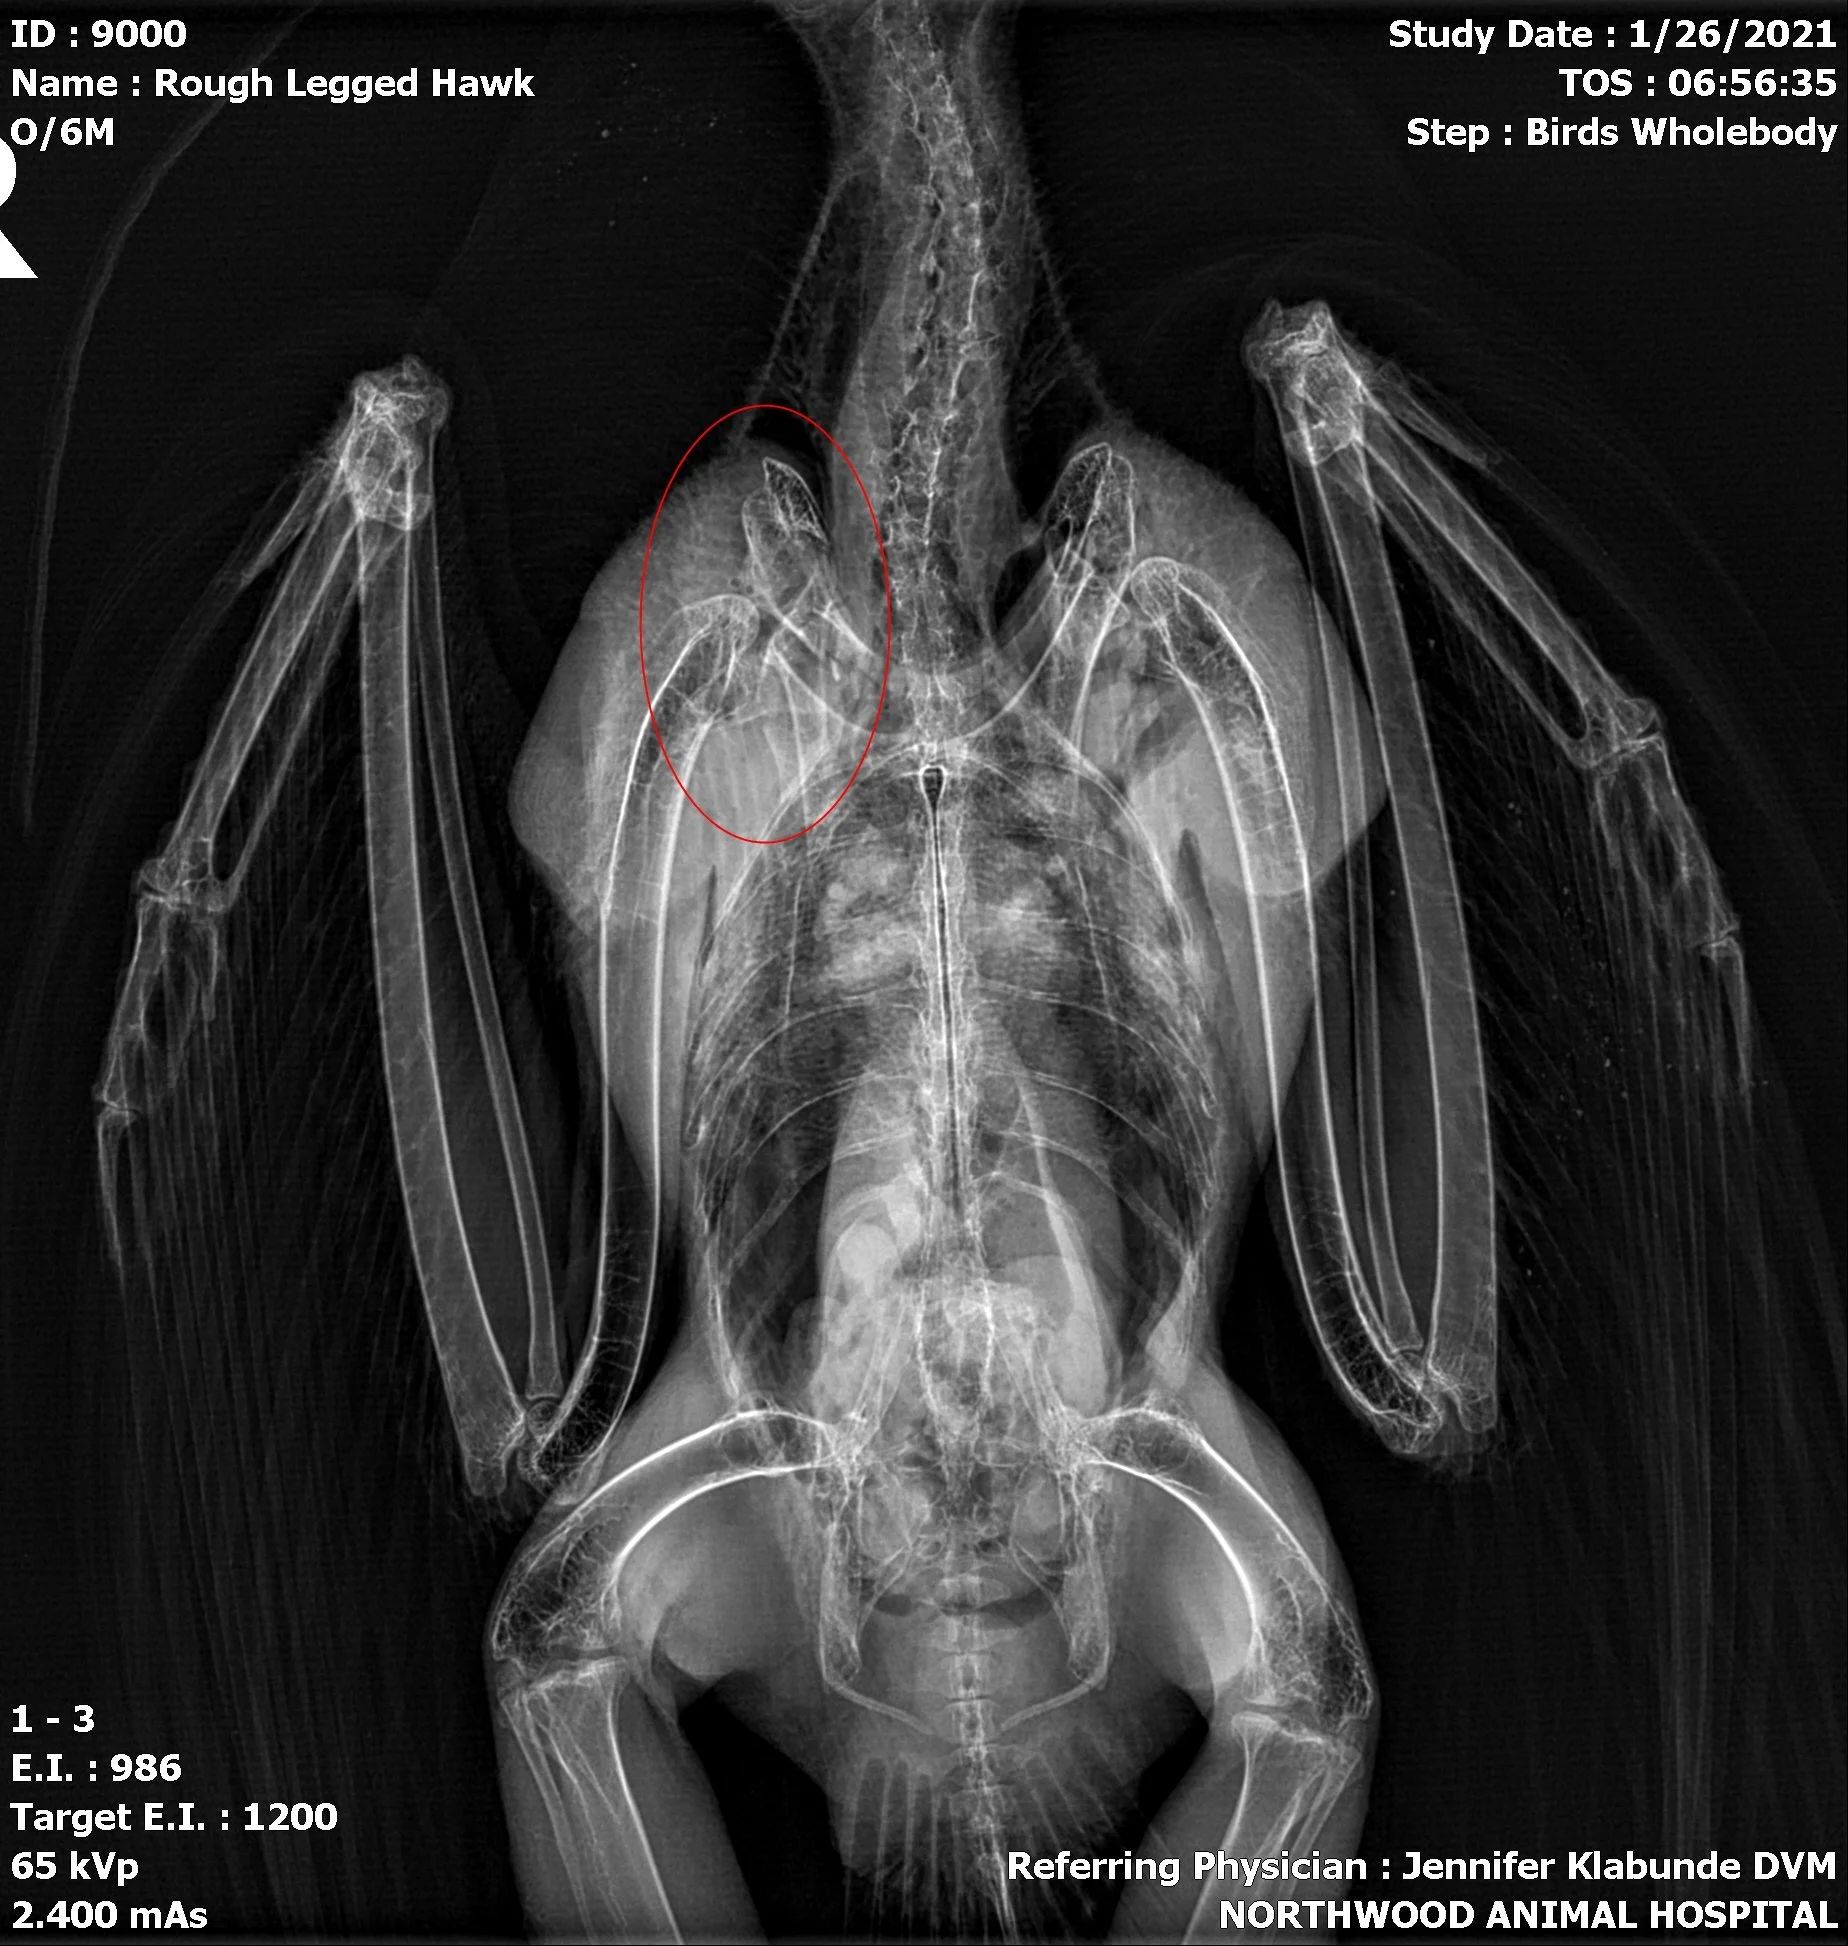

Our services typically begin with our network of trained volunteers and transporters who assist with the rescue and transportation of potential patients. Skilled staff will then complete an intake exam (screening for injuries, parasites, overall health, and any potential disease) which often includes lead testing, blood samples, and any lab work necessary for a proper diagnoses.

Patients will then be assigned treatment. This may consist of any combination of fluid therapy, thermal regulation, diet administration, surgery, physical therapy, feather imping, medications, lead chelation, skill development, and physical reconditioning. We are also fortunate to have a number of veterinary partners, who generously aid our efforts by providing valued resources such as radiology, surgery, and medications.